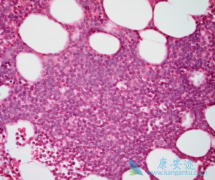

淋巴瘤 ,是起源于淋巴造血系统的恶性肿瘤。发病率约为15/10万,近年来有增长的趋势。淋巴瘤种类繁多,症状也是多种多样。除淋巴结外,淋巴瘤还发生在胃肠道和皮肤等各种器官中,症状因部位而异。一般来说,最常见的症状是淋巴结肿大。通常在淋巴结聚集 ...